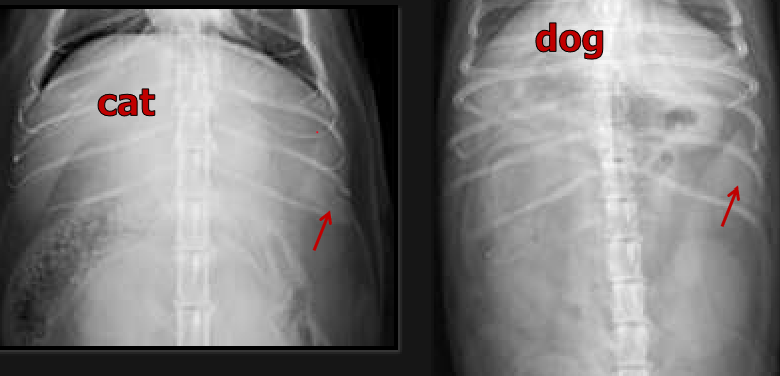

1.6, L5

Dog’s small intestine should be no wider than ____ x height of ____ body

12 mm

Cat’s small intestine should be no wider than ____ in diameter

L7

Large intestine diameter should be less than or equal to the length of ___ on lateral view